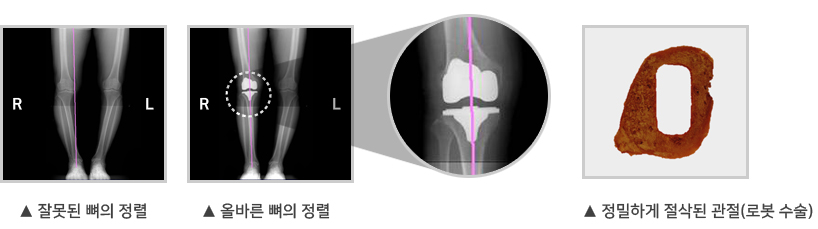

• 인공관절수술 시 뼈의 정렬(MA: Mechanical Axis)이 중요하다는데 이것이 무엇인가요?

뼈의 정렬은 고관절과 슬관절 및 발목의 중심을 잇는 정렬 축이 일직선 상에 정렬된 것을 말합니다.

뼈의 정렬이 잘 이루어지면 체중을 고루 분산시켜 무릎관절이 체중을 지지하는 데 문제가 없습니다.

O다리 X다리의 경우처럼 축이 일직선 상에서 벗어나면 올바른 보행이 어려워 관절질환이 생기기 쉽습니다.

관절질환으로 인해 인공관절수술을 받을 때는 뼈의 정렬을 얼마나 정확히 맞추느냐가 중요합니다.

로봇인공관절수술은 로봇 특유의 정밀함으로 다리뼈의 정확한 정렬이 가능합니다.

정확한 뼈의 정렬은 인공관절 수명을 늘려 재수술률을 낮춰주고 다리의 운동(가동)범위(ROM: Range of motion)도 늘려줄 수 있습니다.

• 서브 밀리미터 치수 정확도와 우수한 정렬을 위한 정밀한 커팅

정확한 뼈 절삭은 우수한 결과를 제공합니다.

큐렉소의 인공관절 수술로봇은 서브 밀리미터 수치의 정확도와 정밀한 절삭으로 환자 다리축의 바른 정렬을 불러와 우수한 수술결과를 보여줍니다.